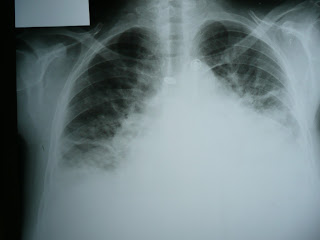

In patients presenting to the ED with undifferentiated dyspnea and a moderate pre-test probability of acute heart failure, a bedside lung U/S and echo are useful diagnostic modalities, with the caveat that there is high inter-operator variability in bedside lung ultrasound.  BNP testing, where available, can be used to help to rule out acute heart failure.  However, the study was limited by numerous methodological issues including study selection, quality of evidence, and significant heterogeneity.